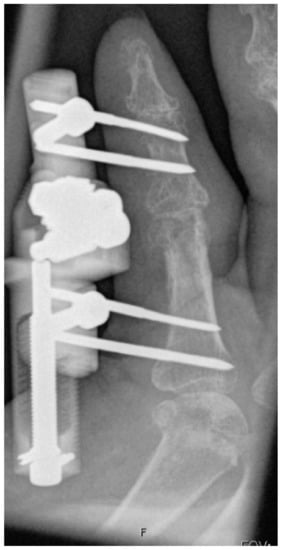

Thirty-one fingers were treated with a staged approach of fasciotomy and skeletal distraction, followed by partial fasciectomy with zigzag-shaped skin incisions [33]. Eleven fingers were satisfactorily treated with palmar fasciotomy and skeletal distraction. Thirteen fingers received simultaneous skeletal distraction combined with partial fasciectomy (Figure 7, Figure 8 and Figure 9).

Figure 7. Intraoperative application of the skeletal distraction device in combination with fasciectomy.

Figure 8. Completely extended PIP joint of the same patient shown in Figure 5, Figure 6 and Figure 7 at 6 weeks of distraction showing complete release of the PIP joint.

Figure 9. Presented patient 8 weeks after fasciectomy.